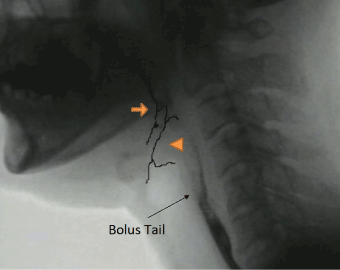

From the viewpoint of the neoglottis morphology, prior to swallowing initiation, the arytenoid cartilages sit on the cricoid cartilage and are already located in an elevated position due to the pexis procedure. Furthermore, in the case of post-SCL swallow, we frequently found that the valleculae were not easily identifiable due to epiglottic approximation to the root of the tongue. These features appeared to make it easier for the arytenoid to make contact with the tongue base (Figure 3). Thus, by the time the bolus has arrived at the PES, the tongue base (attached to the epiglottis) is seen to approximate the arytenoids effectively and rapidly to close the supraglottic passage (Figure 4). Moreover, the supraglottic airway remains closed until after the PES has opened (Figure 5). These findings, which are consistent with the report by Woisard et al. [17], were demonstrated by the prolonged duration of airway closure and PES opening.

Figure 4. Retrofluorographic lateral view at initiation of neoglottic closure from contacting the epiglottis petiole and mucosa of the arytenoid, showing a closed airway